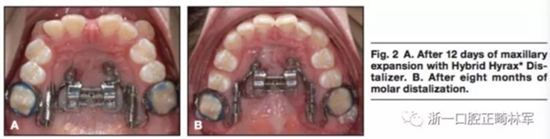

局麻下将两枚2mm*9mm的微种植体植入邻近腭中缝处。在上颌第一前磨牙处使用不锈钢丝。使用聚乙烯硅氧烷上颌取模以制造Hybrid。局麻下翻开粘骨膜瓣使用4枚皮质钉以在下颌前牙放置钛板。通过转动矢状向的螺钉90°4次以激活扩弓器,0.2mm每次,0.8mm每天。钛板使用皮筋在两侧直接加400g前牵力。12天后,上颌前磨牙间横向宽度增加到9mm。(图2,A)矢状螺钉在磨牙远移阶段固定,每周激活双侧远移螺钉(0.2mm每周)。8个月后磨牙远移4mm(图2B),该阶段继续挂皮筋。